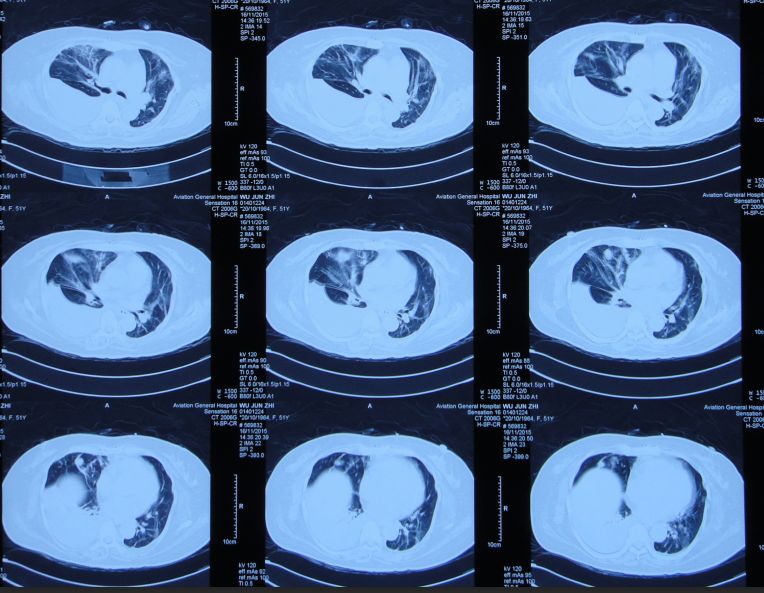

入院后第二天即2014年12月16日为求进一步治疗,患者被转入淮南市某人民医院,查头CT:左额叶脑挫伤、脑组织弥漫性肿胀(图4);胸CT:双下肺感染(图5)。

图5:2014年12月17日胸CT:双下肺感染